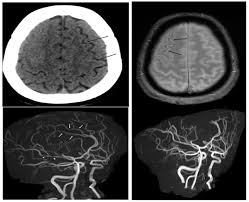

Recurrence Of Reversible Cerebral Vasoconstriction Syndrome Neurology